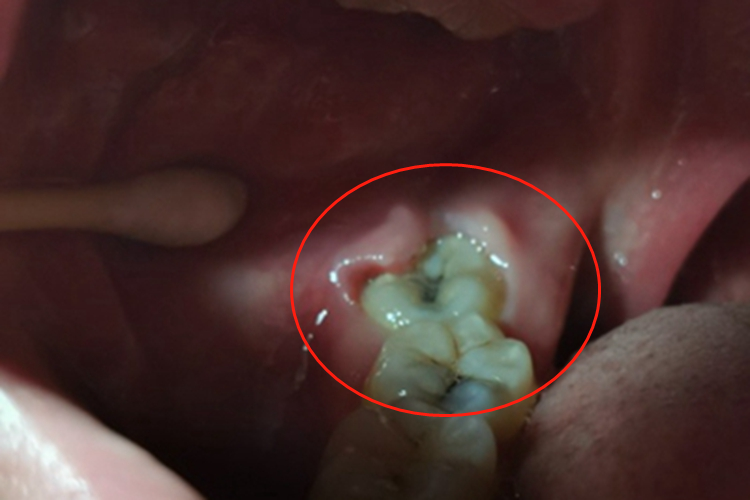

智齿冠周炎发生后,可见患者牙龈出现损害,表现为局部发红、肿胀,甚至糜烂、流脓等。患者自觉疼痛,吞咽、进食时加重,甚至张口受限。

智齿冠周炎主要与口腔卫生差等因素有关。临床上智齿在萌出过程中形成与口腔相通的盲袋,盲袋内易存储食物残渣、唾液、细菌,在适宜的口腔温度和湿度环境中很容易滋生细菌,容易引发冠周智齿炎。